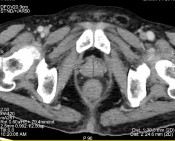

Hình B. Hình ảnh chụp CT sau điều trị 6 tháng

Sau 36 tháng điều trị, bệnh nhân xuất hiện tiểu máu, đau cột sống thắt

Bệnh nhân được xét nghiệm nồng độ PSA 631,3 ng/mL, fPSA 95,75

ng/mL, Testosterone 0 ng/dL.

Bệnh nhân được chụp cắt lớp vi tính toàn thân, kết quả:

- Tuyến tiền liệt không to, không thấy tổn thương xâm lấn ra phía

ngoài.

- Nhiều tổn thương di căn lan toả nhu mô 2 phổi kèm theo lớp dịch

mỏng màng phổi 2 bên.

- Di căn hạch trung thất, hạch sau phúc mạc.

- Nhiều ổ đặc xương thứ phát ở xương sườn 4 phải, xương sườn 8 trái và nhiều đốt sống (thấy rõ ở D12, L2, L5).

Hình C. Hình ảnh chụp CT tại thời điểm kháng cắt tinh hoàn